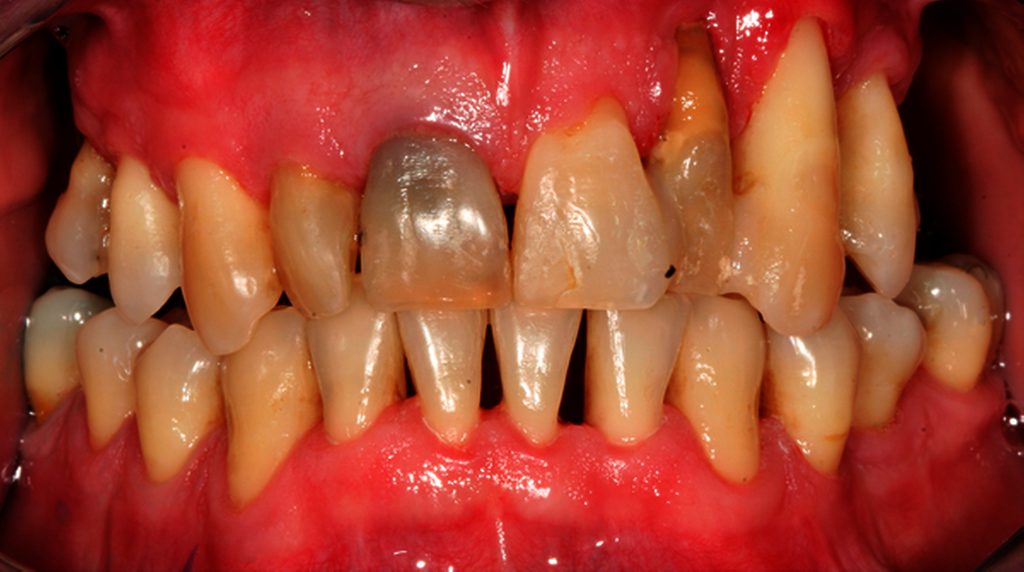

Abb. 2: Professionelle mechanische Plaquereduktion während einer UPT-Sitzung bei einem 50-jährigen Patienten mit reduziertem, aber gesundem Parodont im dritten Jahr nach zweiter Therapiestufe:

Weiterhin sollte bei der Betrachtung der Empfehlungen zu adjuvanten Maßnahmen zur PMPR – wie der antimikrobiellen Photodynamischen Therapie (aPDT) oder alternativer Verfahren wie der Er:Yag-Laseranwendung – beachtet werden, dass sich in der zugrunde liegenden systematischen Analyse von klinischen Studien von Trombelli et al. für diese Verfahren keine größeren klinischen Effekte nachweisen ließen [Trombelli et al., 2020].